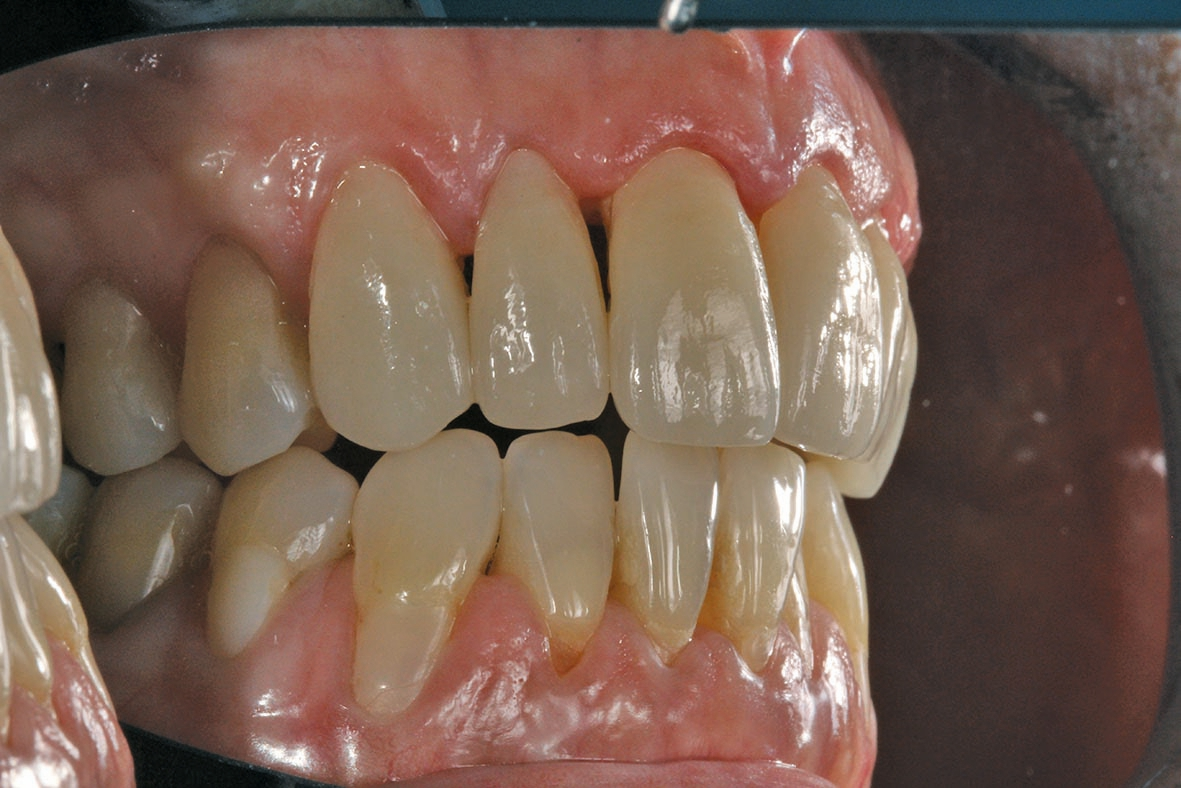

Die fertigen Veneers im Patientenmund